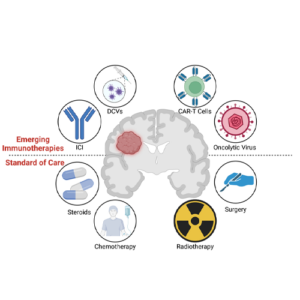

Advanced & Emerging Colorectal Cancer Treatments in Germany

Dendritic Cell Therapy for Colorectal Cancer

– Dendritic cell (DC) therapy enhances the immune response, helping prevent recurrence in high-risk cases.

Best for:

Stage 2 colorectal cancer with high-risk features.

Post-surgical patients seeking immune-boosting therapy.

Cost: €40,000 – €55,000 per treatment plan

Success Rate: Boosts long-term immune defense against recurrence.